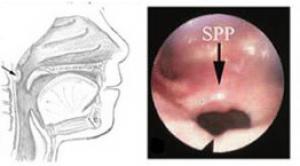

Sphincter pharyngoplasty

In a sphincter pharyngoplasty, tissue from the sides of the throat are used to create a pad of tissue on the back of the throat. This narrows the airway passage into the nose, reducing air flow through the nose during speech.